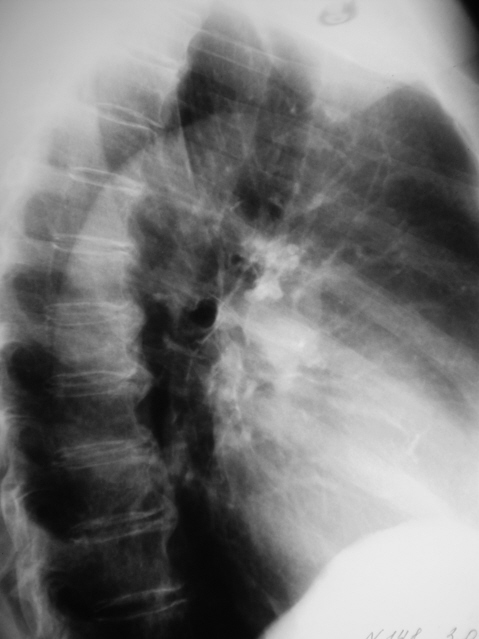

Периферический рак. Томография. Множественный распад.